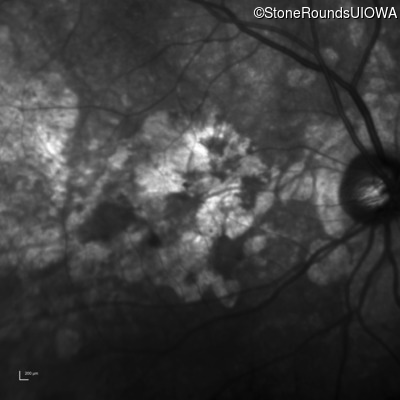

Infrared Fundus Photograph - Right - 20/200 +2

Exemplar